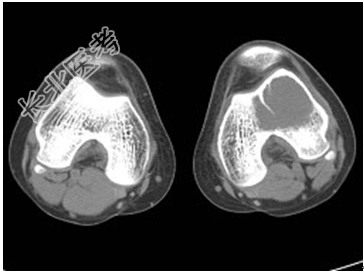

- [材料题] 患者,男,33岁,左股骨肿块半年余,无明显症状,查体一般情况良好。

- 简答题1、结合所提供的图像,该患者诊断为?

- 1、该患者诊断是?2、该疾病的治疗原则是